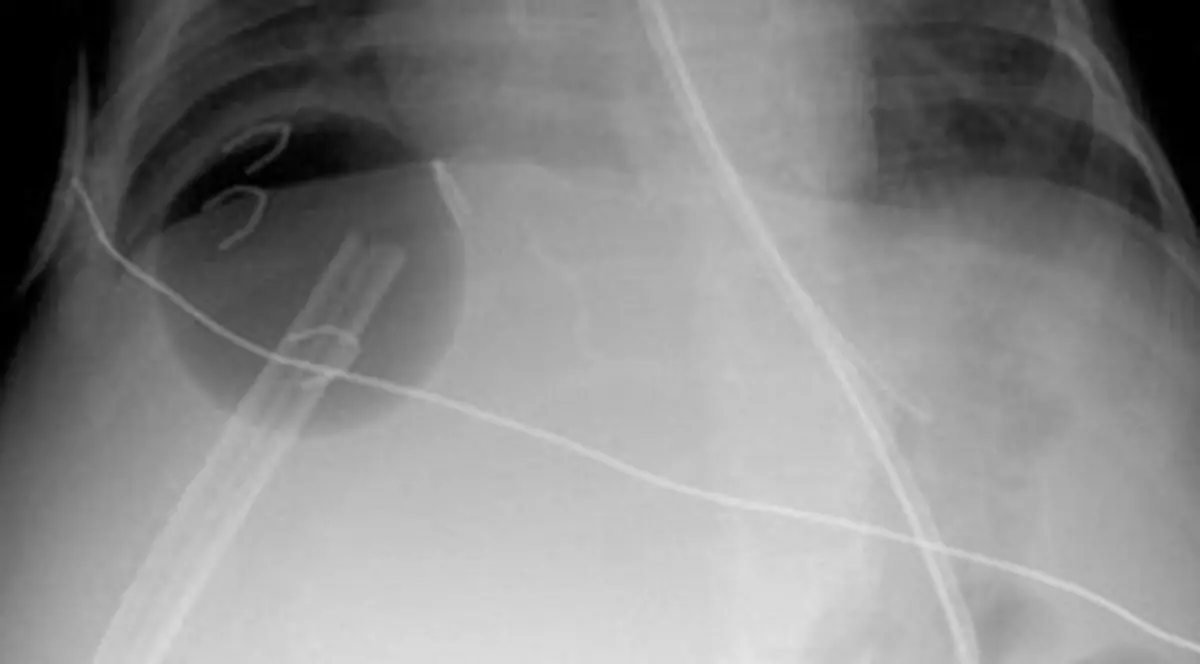

Astfel, medicul s-a gândit să aplice o metodă ”neconvenţională” pentru a încerca să salveze viaţa micuţei. Shun a luat o minge de ping-pong, pe care i-a fixat-o fetei sub ficat, pentru a susţine organul. Medicul nici nu i-a anunţat pe părinţii lui Mackenzie despre procedura inedită, decât după ce pacienta a fost externată.

Mama micuţei a simţit că i se taie picioarele când a aflat că în corpul copilei se află o minge de ping-pong, care va rămâne acolo. Întrebat dacă nu există pericolul ca fetiţa să facă infecţie de la obiectul care i-a salvat viaţa, doctorul a afirmat că mingea va fi foarte bine tolerată de organism, iar cu timpul, ficatul va creşte în jurul ei.